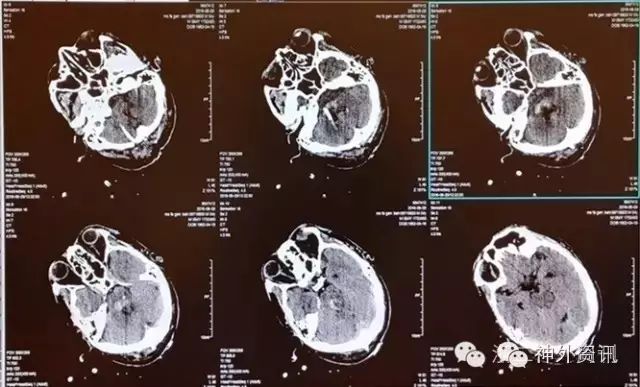

术中所见(视频2):术中抽出血肿约15ml并血肿腔灌洗。术后动态复查CT评估血肿残余量及脑室扩张情况(图4,图5),分别于术后第1、3天予3万单位尿激酶灌注溶血。术后第4天复查CT示血肿排空满意,脑室无扩张(图6),予拔管引流管并暂停镇静药。随后患者呼之能应,点头或摇头配合,右侧肢体遵嘱能动,术后第11天转回普通病房,术后2周病情稳定(视频3),转康复治疗。

图5. 术后第二天复查CT,示血肿进一步减少。

图6. 术后第4天CT,显示血肿排空良好,脑室大小正常。